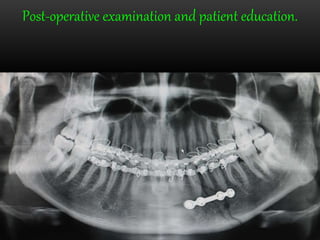

Post-operative examination and patient education.